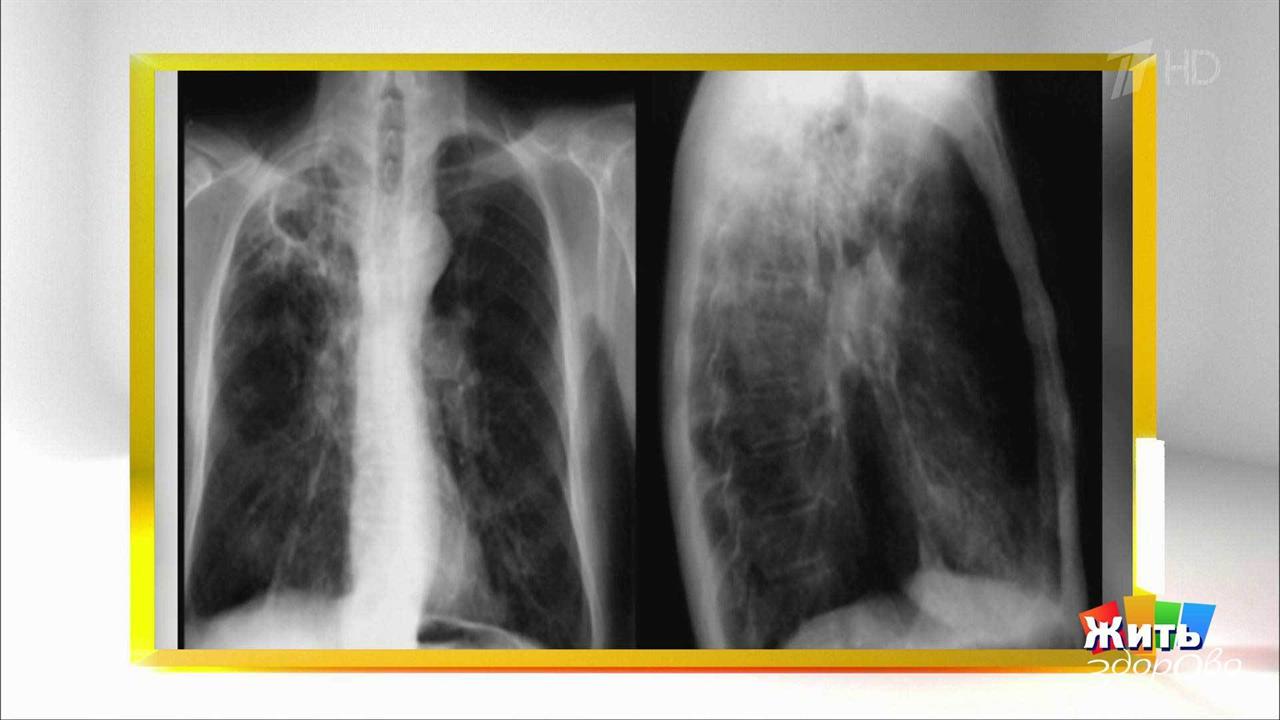

Туберкулез. Казалось, мы забыли об этой болезни, но в последнее время она подняла голову в России и во всем мире. Елена Малышева пригласила врача-фтизиатра Андрея Марьяндышева, чтобы он в студии ответил на популярные вопросы о туберкулезе. Правда ли туберкулез – болезнь нищих и бездомных? Опасен ли носитель палочки Коха для окружающих? Заразны ли больные туберкулезом? Туберкулез – это исключительно легочное заболевание? Он неизлечим? Что лучше – диаскинтест или реакция Манту?